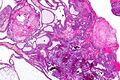

Adamantinomatous craniopharyngioma - very low mag.jpg

Very low magnification micrograph of an adamantinomatous craniopharyngioma. HPS stain.

في بعض الحالات ، يمكن أن يساعد ماسح التصوير بالرنين المغناطيسي القوي 3T (Tesla) في تحديد موقع هياكل الدماغ الهامة المتأثرة بالورم. يتكون النمط النسيجي من تعشيش ظهارة حرشفية تحدها خلايا مرتبة بشكل اشعاعي. غالبًا ما يكون مصحوبًا بترسب الكالسيوم وقد يكون له بنية حليمية مجهرية. يعد التصوير المقطعي المحوسب (CT) أيضًا أداة تشخيصية جيدة ، حيث يكتشف التكلس في الورم..[20]

في الفحص العياني ، يكون الورم القحفي البلعومي كيسيًا أو كيسيًا جزئيًا مع مناطق صلبة. في المجهر الضوئي ، يُنظر إلى الأكياس على أنها مبطنة بظهارة حرشفية طبقية. يمكن أيضًا رؤية لآلئ الكيراتين. تمتلئ الأكياس عادة بسائل أصفر لزج غني ببلورات الكوليسترول. من بين قائمة طويلة من الأعراض المحتملة ، تشمل العروض المجيئية الأكثر شيوعًا الصداع ، وفشل النمو ، والعمى نصفي صدغي مزدوج .